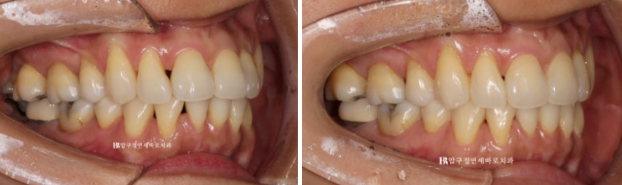

23.04~23.08

비스듬한 측면에서 봤을 때에도 블랙트라이앵글이 많이 줄어든 것이 보입니다.